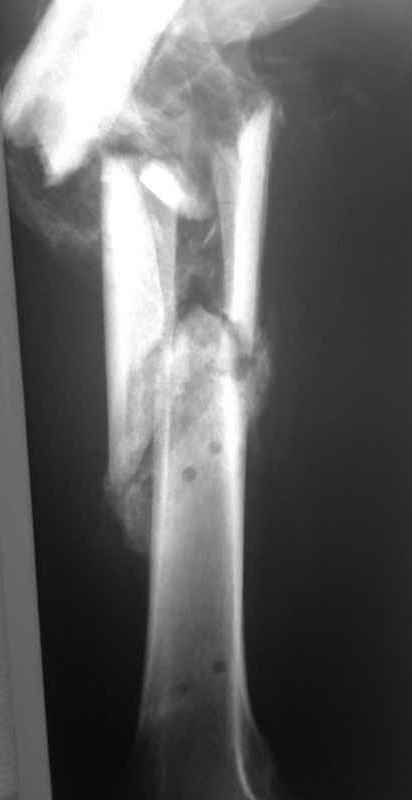

Пациент 39 лет. Травма в ДТП 2.5 месяца назад. Тяжелая сочетанная травма. ЗЧМТ. Тупая травма живота. Разрыв селезенки. Надрывы печени. Перелом бедра. При поступлении лапаротомия. Спленэктомия. Фиксация перелома бедра стержневым аппаратом. в последующем инфаркт мозга на фоне жировой эмболии. длительное нахождение на ИВЛ. Обширный пролежень в области крестца. и т.д.в настоящее время состояние больного стабилизировалось. активизирован на ходунках.имеется деформация бедра, укорочение 10 см. гранулирующий пролежень в области крестца. патологической подвижности в зоне перелома не отмечается.Оптимальные сроки проведения реконструктивной операции на бедре? Сейчас? Или после окончательного сращения?

Конечно, снимки для планирования надо нормальные, не такой огрызок.

Спасибо за снимки. Предложения по тактике прежние.

Попробовать-то можно. И просто руками "об колено", а то и наложить аппарат, приложить флексионные и ротационые усилия прямо за разъединенные секции.

Но если картинки недавние, IMHO должно получиться закрыто разобщить.